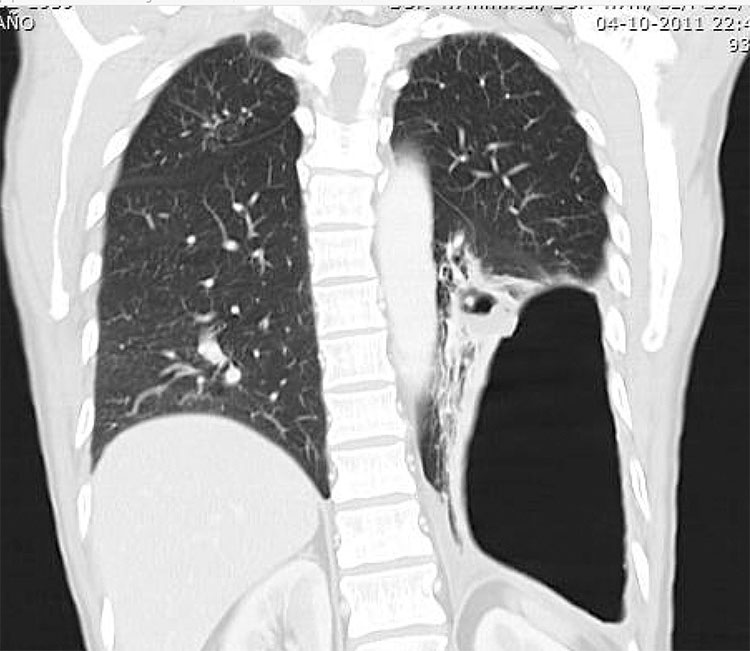

Las cavitaciones tuberculosas ocurren más comúnmente en áreas de consolidación e indican muy sugerentemente que se encuentra una infección activa, son a menudo múltiples y de paredes irregulares y gruesas (Figs. 10, 11 y 12).15,16,17 Es extraño encontrar niveles hidroaéreos, pero cuando se hallan, sugieren la posibilidad de una sobreinfección (Fig. 10).18,19

Hombre de 32 años, con antecedentes de TBC pulmonar, con reactivación de su cuadro, se solicitó TC de tórax, donde se destacó: pulmón izquierdo disminuido de volumen con severa distorsión de la arquitectura pulmonar, con bronquiectasias varicosas y un mínimo remanente de parénquima normal en el lóbulo inferior izquierdo, se aprecian cavitaciones de distintos tamaños (flecha). En el pulmón derecho persisten imágenes de "árbol en brote" (triángulo), asociado a opacidades pulmonares y focos de condensación. Derrame pleural laminar a izquierda.

El curso natural de la enfermedad progresa a compromiso lobar y opacidades pulmonares casi completas, asociado a destrucción parenquimatosa (Fig. 11), se produce la llamada enfermedad fibroproliferativa, con engrosamientos reticulares y nodulares.17

La diseminación endobronquial es la complicación más común causante de las cavitaciones tuberculosas, que representan una infección granulomatosa crónica en la cual los organismos activos extienden una necrosis caseosa de las paredes bronquiales (Figs. 10 y 11).17 Los hallazgos en TC se manifiestan como opacidades pequeñas y mal definidas, nodulillares centrilobulares sugiriendo la apariencia de un “árbol en brote” (Figs. 10, 11 y 12).20,21